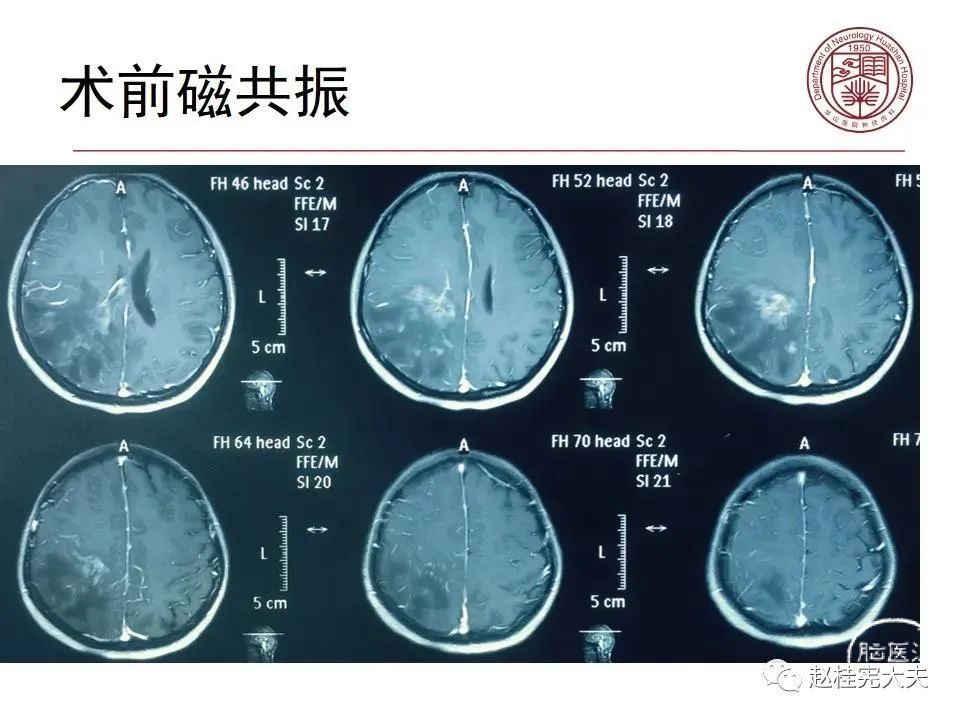

患者女性,19岁,反复头痛数年,近期加重伴记忆力下降,反复查磁共振报正常。结合病史,仔细阅片发现大脑皮层Flair、DWI异常信号。抽血查血清MOG抗体1:32,诊断MOG皮层脑炎。